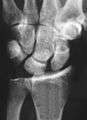

Scapholunate disassociation